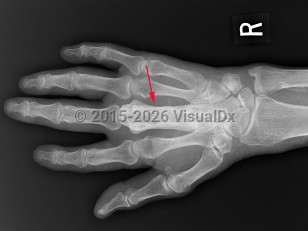

Paget disease is caused by increased bone remodeling and focal bone growth. It is a disease of osteoclasts that is generally seen in older adults and typically affects the skull, spine, pelvis, and long bones of the lower extremities. A common finding associated with aging, Paget disease is identified in 2%-9% of elderly patients, with age of onset at 55 years.

The disease is often asymptomatic but can cause bone pain, fractures, bone deformity, and symptoms due to compression of surrounding structures (eg, hearing loss, lumbar radicular pain). Genetics and viruses are suspected to play a role in causing the disease.